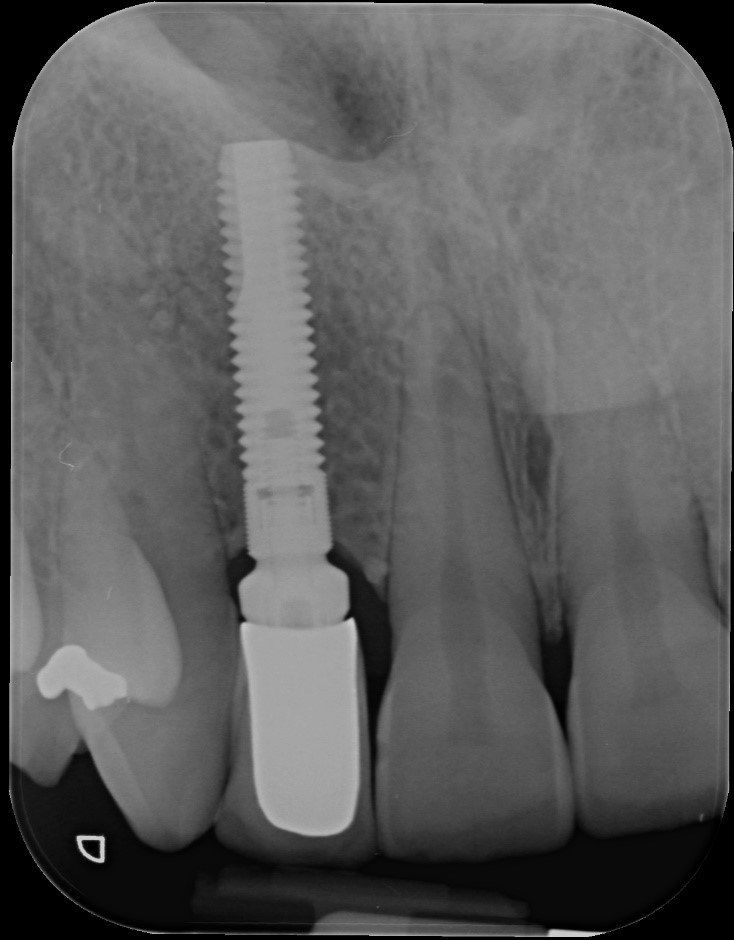

Visione clinica del Maryland bridge cementato con tecnica adesiva ed immagine tomografica tridimensionale per valutare lo spessore bucco palatale utile all’inserimento dell’impianto che fu valutato come sufficiente benchè esiguo. A tal proposito deve essere sottolineato che la letteratura consiglia, quando è disponibile un volume di osso residuo utile all’inserimento di un impianto, di evitare tecniche di innesto osseo in quanto un aumento dei volumi ossei non migliora la prognosi estetica (3)